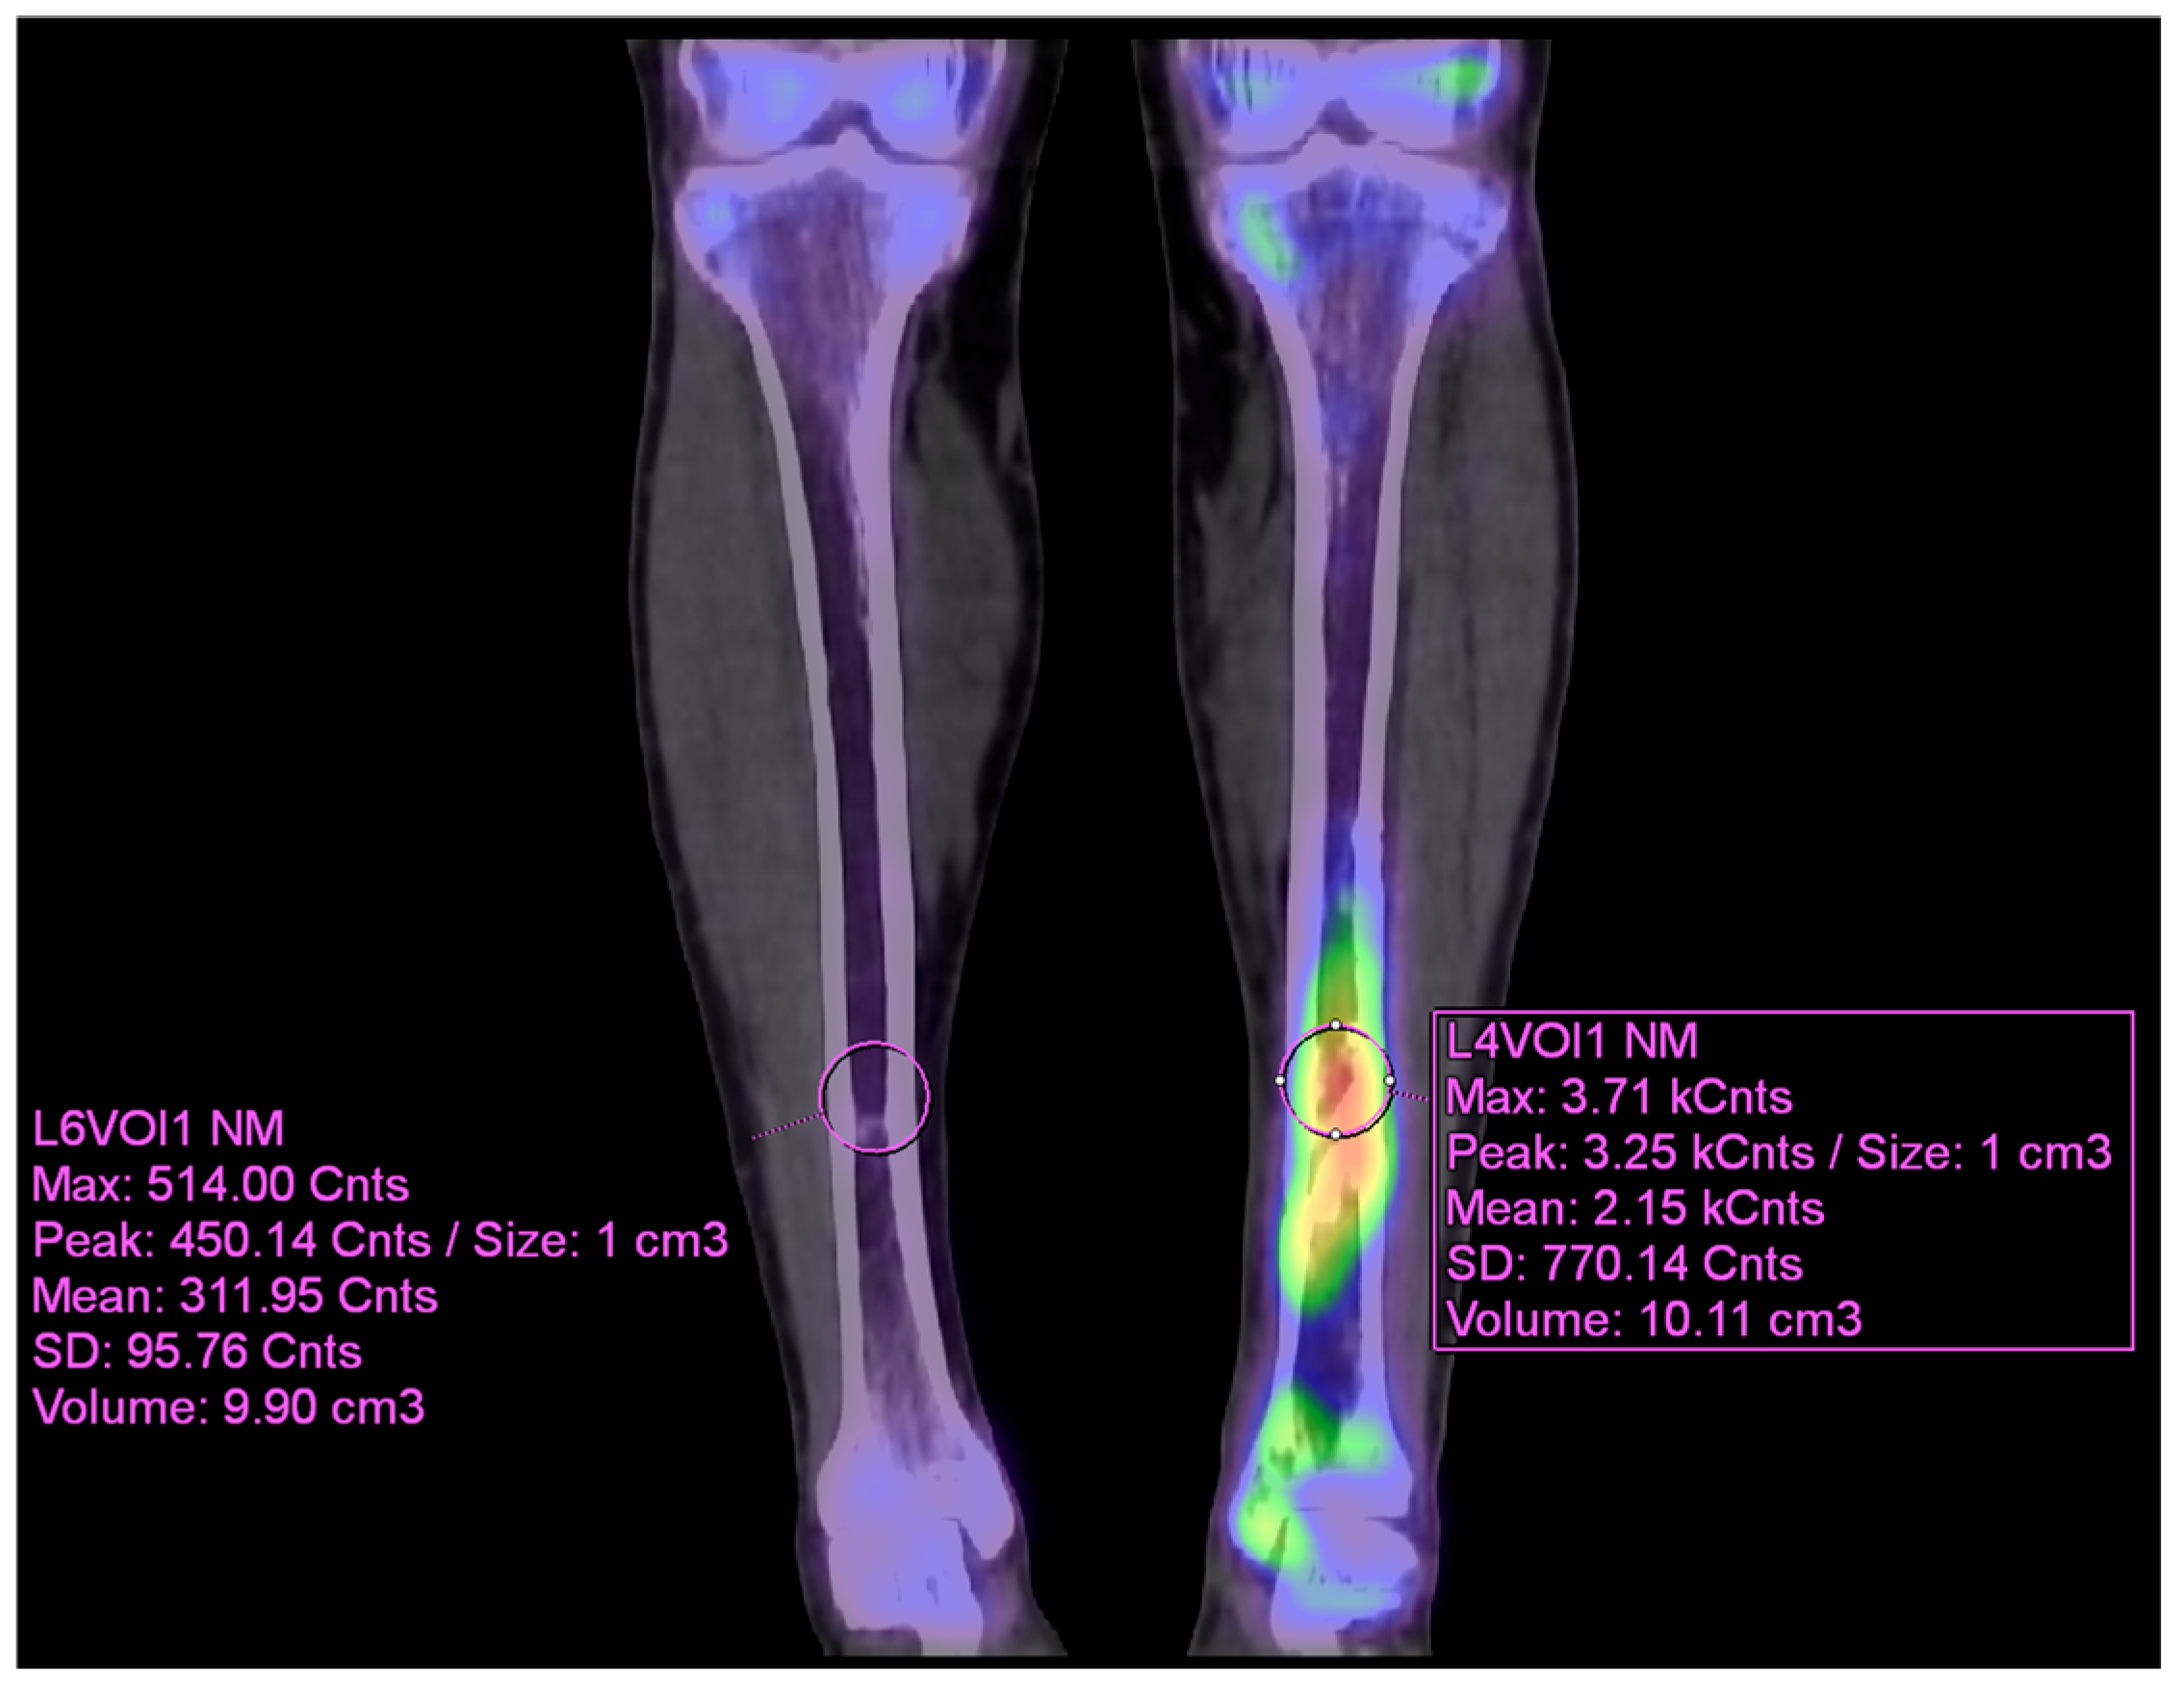

As the infection did not improve, the patient visited our outpatient clinic. He had been receiving intravenous and oral ciprofloxacin for 10 months since the 8-month postoperative day. After the initial visit to our clinic, 99mTc DPD bone SPECT/CT scan was performed, revealing areas of increased uptake, as shown in the images below (Figure 5 and Figure 6).

Figure 6. VOI (volume of interest) analysis of preoperative 99mTc DPD bone SPECT/CT coronal image (contralateral side and affected side) using Syngo.via.